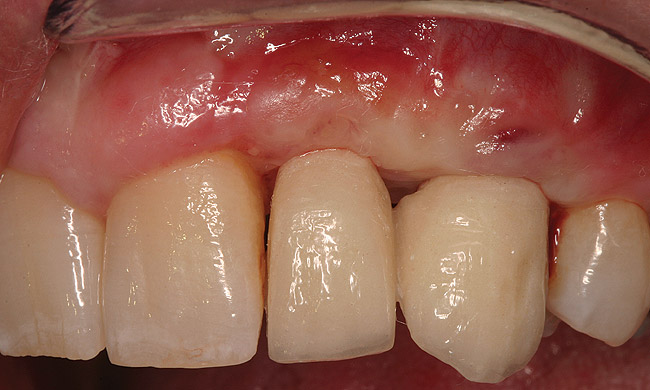

Figure 21  (Case 2) Final implant restoration with adjacent crowns following surgical crown lengthening.

Figure 21

Figure 22  (Case 2) Final smile with anterior restorations in place.

Figure 22